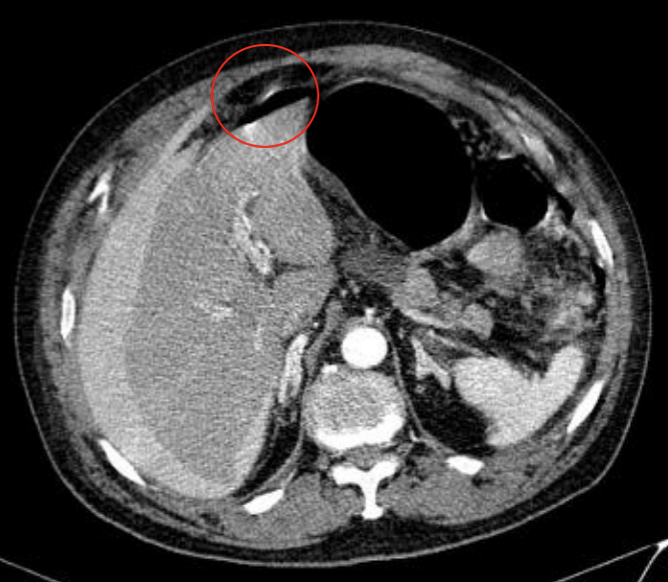

A

TC de neumoperitoneo